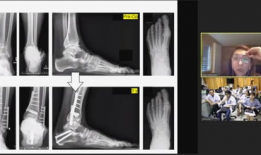

骨科视频,常见骨折与手术技巧全解析

亲爱的读者们,你是否曾因为关节疼痛而烦恼不已?又或者,你身边有没有朋友正在经历骨科疾病的困扰?今天,就让我带你走进一个全新的世界...